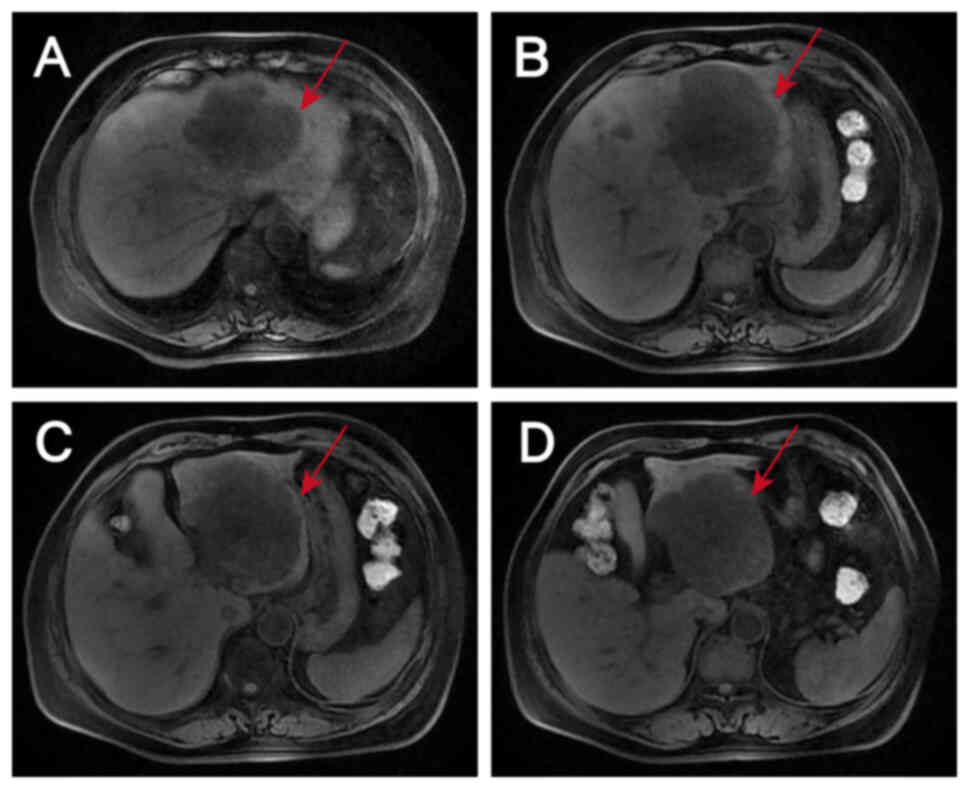

Metastatic liver lesions after 6

cycles of anti-HER2 therapy combined with chemotherapy as assessed

by magnetic resonance imaging on April 10, 2024. When compared with

the images captured on January 25, 2024, (A-C) the larger

metastases in S2, S3 and S4 have decreased in size, while the

smaller metastasis appears unchanged. (D) No changes in the two

enlarged lymph nodes anterior and posterior to the portal vein are

evident.

Figure 9.

Metastatic liver lesions after 6 cycles of anti-HER2 therapy combined with chemotherapy as assessed by magnetic resonance imaging on April 10, 2024. When compared with the images captured on January 25, 2024, (A-C) the larger metastases in S2, S3 and S4 have decreased in size, while the smaller metastasis appears unchanged. (D) No changes in the two enlarged lymph nodes anterior and posterior to the portal vein are evident.

EGFR inhibitor therapy was not considered due to the NGS result and the evidence suggesting that patients with HER2-positive CRC are highly resistant to EGFR inhibitors (11,12). Furthermore, targeted bevacizumab therapy was not started because hemorrhage is one of the most serious adverse effects of bevacizumab and the patient had persistent hematochezia. In light of the recent developments in CRC research and the financial circumstances of the patient, single-agent anti-HER2 therapy combined with a modified FOLFOX6 regimen was selected as the subsequent treatment, in which the doses of chemotherapeutic agents were adjusted and administered on a 3-week cycle. The patient received six cycles of trastuzumab 450 mg + FOLFOX, with the latter comprising oxaliplatin 150 mg + leucovorin calcium 600 mg + fluorouracil 0.625 g by injection + fluorouracil 4 g by continuous intravenous drip. These agents were administered on 41 days post admission, 62 days post admission, 83 days post admission, 108 days post admission, 134 days post admission, and 157 days post admission. During treatment, the tumor marker levels gradually decreased (Fig. 4), and computed tomography (CT) and magnetic resonance scans of the liver indicated a marked reduction in the size of the tumor lesions (Fig. 6, Fig. 7, Fig. 8, Fig. 9). This was evaluated as a partial response.